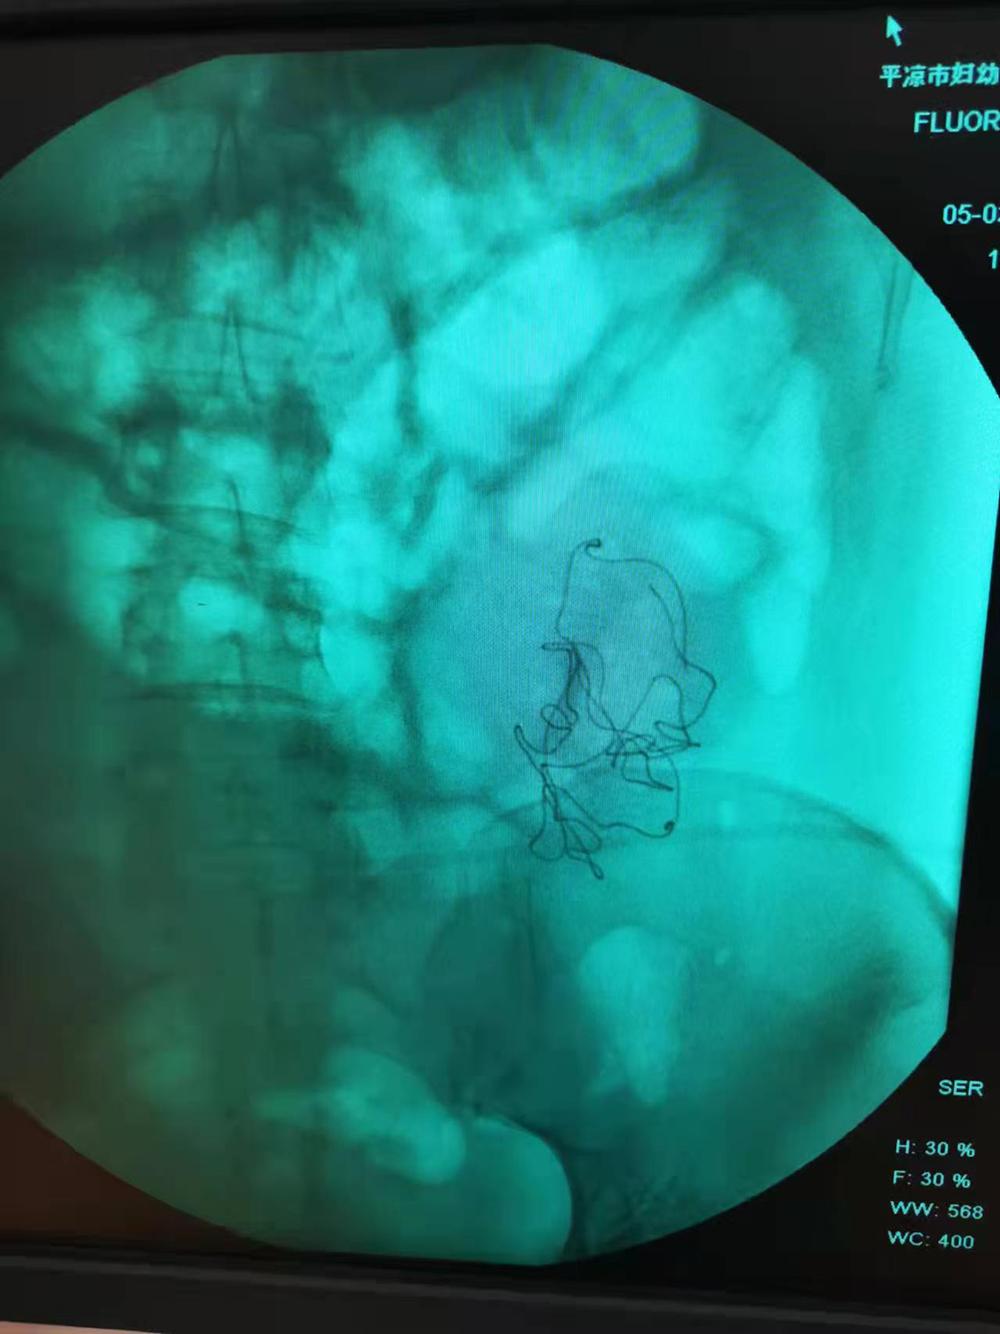

在秦红利多次请求下,院方终于将当时的检查影像交给了她。影像中,腹腔内异物影清晰可见。然而,在当天的手术记录中,这一异常没有留下任何痕迹。

秦红利分娩后,进行X光检查发现异物清晰可见。本文图片均为 受访者供图

手术记录中,二次开腹的原因是腹腔渗血,并写道:“因病情紧急在产房行急诊剖宫产术,为确保病人安全急行X线透视以观察腹腔内情况,X线透视显示有少量液平面,考虑血管收缩渗血可能,遂入手术室在静脉麻下行腹腔探查,发现腹膜一小血管渗血立即缝扎止血,再次探查腹腔无异常遂常规关腹”。